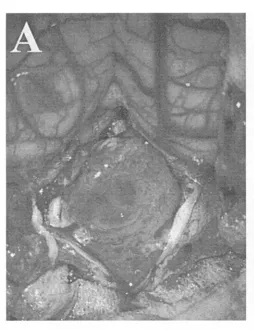

巴特朗菲教授首先使用CUSA刀对肿瘤进行减容处理,逐步为关键神经血管结构创造操作空间。随后在显微镜下完成高度精细的肿瘤切除手术:完整游离尾组颅神经根丝、椎动脉(VA)近端及PICA分支。

(A)硬脑膜切开后可见向下延伸至C1水平的大型肿瘤;

尽管肿瘤已侵犯脑干,巴教授仍在第四脑室底部坚持彻底切除,以预防复发,并进行细致止血。研究证据表明,术后CT或MR影像学检查无肿瘤残留是长期生存的有利预后因素。

(E)小脑延髓外侧池内结构保持完整,箭头指示右侧椎动脉;